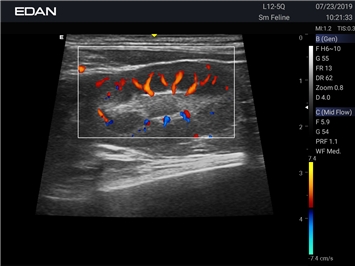

Недопплеровская визуализация кровотока:

Да

Цветовой допплер:

Направленный энергетический допплер: